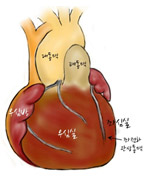

[그림1] 정상 심장

대동맥이 폐동맥보다 후방에 위치하며 우심실에서 폐동맥이 기시하고 대동맥은 좌심실에서 기시함